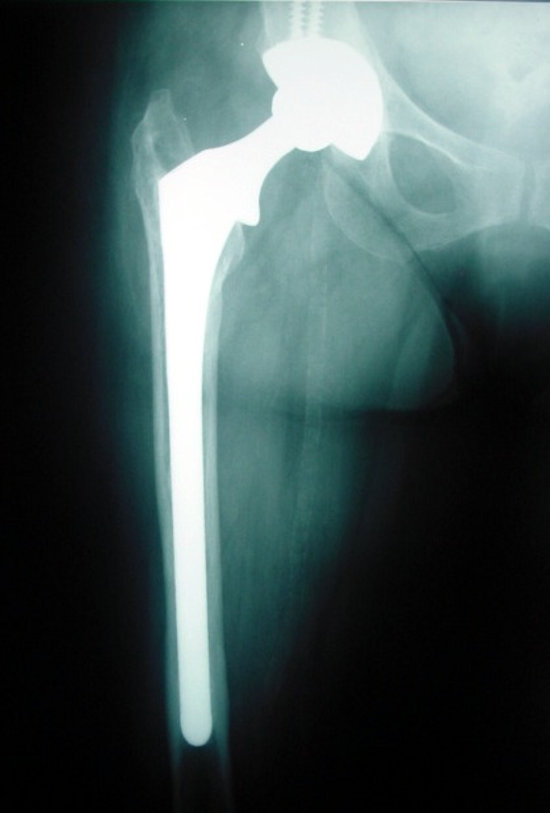

Kalça protezi kemiğe iki şekilde tutturulabilir. Kemik kalitesi çok iyi olmayan ileri yaştaki hastalarda, protez kemik çimentosu adı verilen bir dolgu maddesi ile kemiğe tespit edilir. Bu tip protezlere çimentolu kalça protezi adı verilir. Kemik kalitesi iyi olan daha genç hastalarda ise, üzeri gözenekli bir madde ile kaplanmış olan protezler, kemiğin içine çok sıkı bir şekilde yerleştirilir ve sonrasında vücudun kemiği, protezin üzerindeki gözeneklerin içine ilerleyerek tespiti sağlar. Bu tip protezlere çimentosuz kalça protezi adı verilir.

Erken kalça protezi tasarımları sadece kemik çimentosu ile tespite izin verirken, günümüzde buna çimentosuz kalça protezleri de eklenmiştir. Böylece protezin, bir dolgu maddesine gerek olmadan doğrudan kemiğe tutunması imkanı sağlanmıştır.